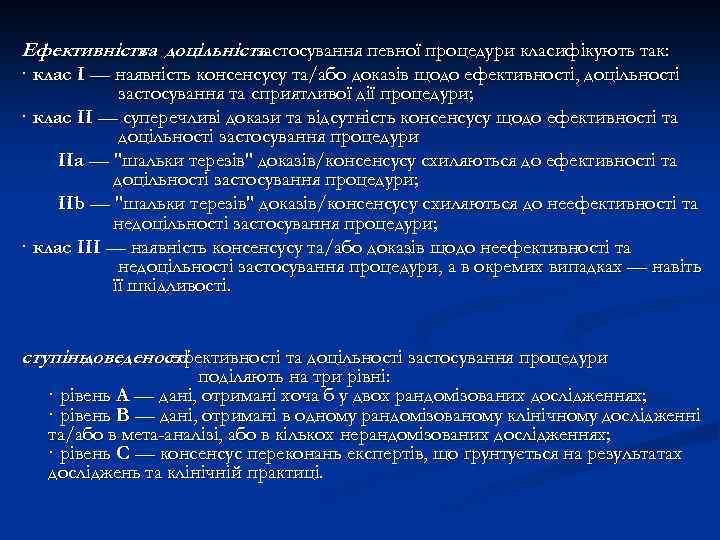

Ефективність доцільність та застосування певної процедури класифікують так: · клас І — наявність консенсусу та/або доказів щодо ефективності, доцільності застосування та сприятливої дії процедури; · клас ІІ — суперечливі докази та відсутність консенсусу щодо ефективності та доцільності застосування процедури ІІа — "шальки терезів" доказів/консенсусу схиляються до ефективності та доцільності застосування процедури; ІІb — "шальки терезів" доказів/консенсусу схиляються до неефективності та недоцільності застосування процедури; · клас ІІІ — наявність консенсусу та/або доказів щодо неефективності та недоцільності застосування процедури, а в окремих випадках — навіть її шкідливості. ступінь доведеності ефективності та доцільності застосування процедури поділяють на три рівні: · рівень А — дані, отримані хоча б у двох рандомізованих дослідженнях; · рівень В — дані, отримані в одному рандомізованому клінічному дослідженні та/або в мета-аналізі, або в кількох нерандомізованих дослідженнях; · рівень С — консенсус переконань експертів, що ґрунтується на результатах досліджень та клінічній практиці.

Ефективність доцільність та застосування певної процедури класифікують так: · клас І — наявність консенсусу та/або доказів щодо ефективності, доцільності застосування та сприятливої дії процедури; · клас ІІ — суперечливі докази та відсутність консенсусу щодо ефективності та доцільності застосування процедури ІІа — "шальки терезів" доказів/консенсусу схиляються до ефективності та доцільності застосування процедури; ІІb — "шальки терезів" доказів/консенсусу схиляються до неефективності та недоцільності застосування процедури; · клас ІІІ — наявність консенсусу та/або доказів щодо неефективності та недоцільності застосування процедури, а в окремих випадках — навіть її шкідливості. ступінь доведеності ефективності та доцільності застосування процедури поділяють на три рівні: · рівень А — дані, отримані хоча б у двох рандомізованих дослідженнях; · рівень В — дані, отримані в одному рандомізованому клінічному дослідженні та/або в мета-аналізі, або в кількох нерандомізованих дослідженнях; · рівень С — консенсус переконань експертів, що ґрунтується на результатах досліджень та клінічній практиці.